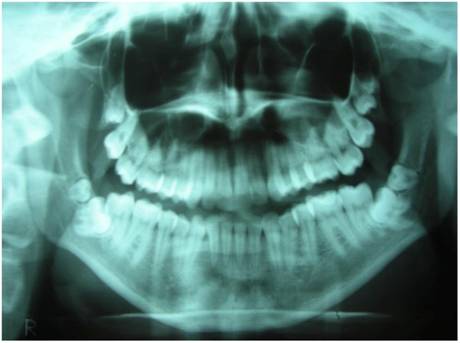

Figure 4

X-Ray Dental Panoramic Tomogram (elder sister)

The radiologic evaluation of the two sisters allowed to determine as follows:

The elder sister had nine impacted teeth; these were 1.8 - 1.9 - 2.8 - 2.9 - 2.10 - 3.8 - 3.9 - 4.8 - 4.9 (Fig. 4), while the youngest sister had four impacted teeth, that is 1.8 - 1.9 - 2.8 - 2.9 (Fig. 5).